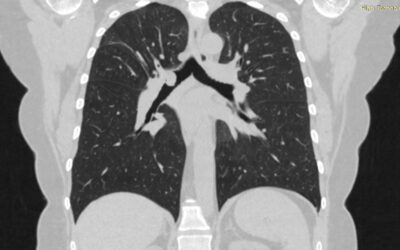

გიგანტური ბულის სარქვლოვანი ბრონქობლოკაცია

პაციენტი 45 წ ქალბატონი. 2022 წ თებერვალში გადაიტანა კოვიდ - 19 მძიმე ფორმაში სტაციონარის რეანიმაციულ განყოფილებაში, სადაც უტარდებოდა ოქსიგენოთერაპია CPAP da BiPAP რეჟიმებში. გამოწერიდან მალევე გაუჩნდა ჰაერის უკმარისობა, ქოშინი ფიზიკურ დატვირთვაზე, შემაწუხებელი მშრალი...